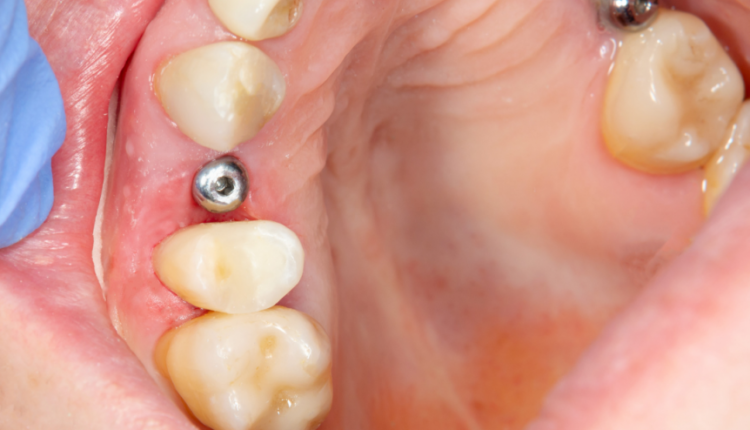

How many steps are in a dental implant?

In general, there are three steps in dental implant placement. First, the implant itself is placed in the jawbone. Next, the abutment is placed on the implant to which the artificial tooth will be attached. Finally, the prosthetic tooth or crown is placed on the abutment.

How long does stage 2 of a dental implant last? In phase 2, the artificial root is placed in the bone and allowed to heal. The procedure itself takes 1 to 2 hours and the healing time is 3 to 6 months. During this time, the titanium alloy implant (the same material used in joint replacement) heals and fuses with the surrounding bone tissue.

The three phases of dental implant surgery Placement of the implant. Attachment of the abutment. Attaching the crown.

- First step: inserting the implant. The first stage of the dental implant process is to surgically bury the implant in the jawbone. …

- Step Two: Placement of the abutment. …

- Step three: The prosthetic tooth.